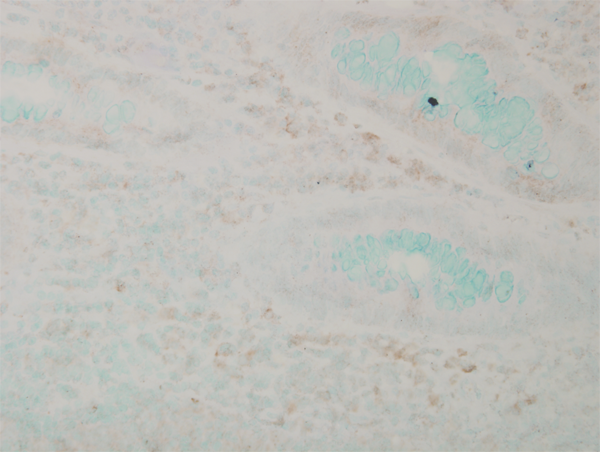

IHC (Immunohiostchemistry)

(Immunohistochemistry analysis using Mouse Anti-p38 MAPK Monoclonal Antibody, Clone 9F12. Tissue: colon carcinoma. Species: Human. Fixation: Formalin. Primary Antibody: Mouse Anti-p38 MAPK Monoclonal Antibody at 1:10000 for 12 hours at 4 degree C. Secondary Antibody: Biotin Goat Anti-Mouse at 1:2000 for 1 hour at RT. Counterstain: Mayer Hematoxylin (purple/blue) nuclear stain at 200 ul for 2 minutes at RT. Magnification: 40x.)